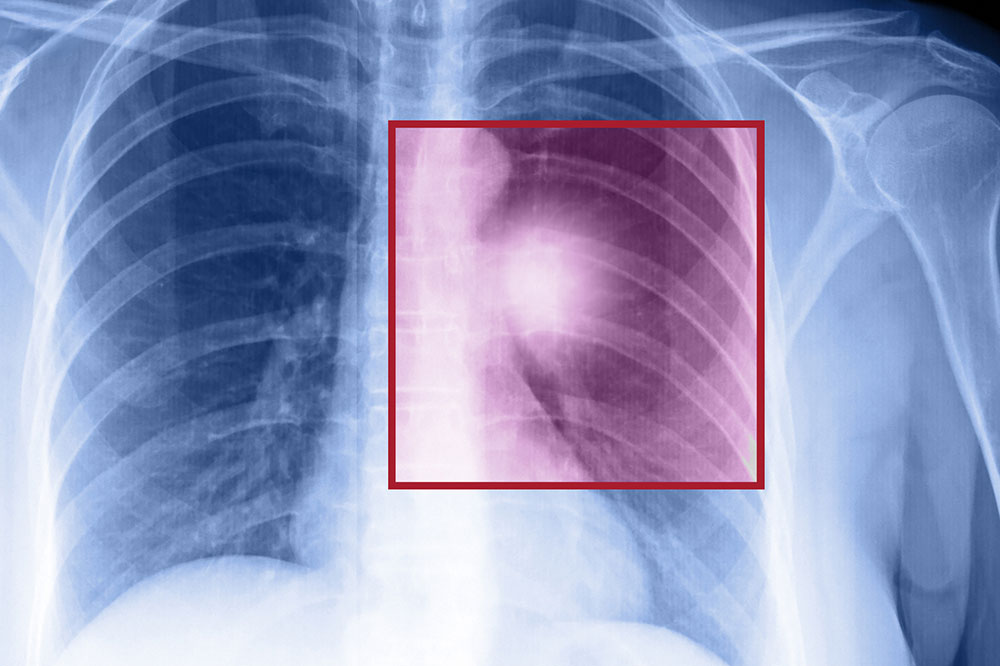

Lung cancer – Types, symptoms, and causes

When the cells in the lungs begin to abnormally multiply and grow, it results in cancer. Lung cancer is one of the leading causes of death in the world. And the risk of suffering from this life-threatening disease is even higher when one is a smoker. Herein, we discuss the various factors that come into play when it comes to lung cancer.